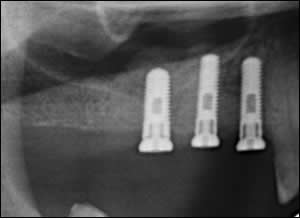

Fig 3: Post-operative radiographs reveals placement of 3 dental implants after “non-surgical” sinus elevation.